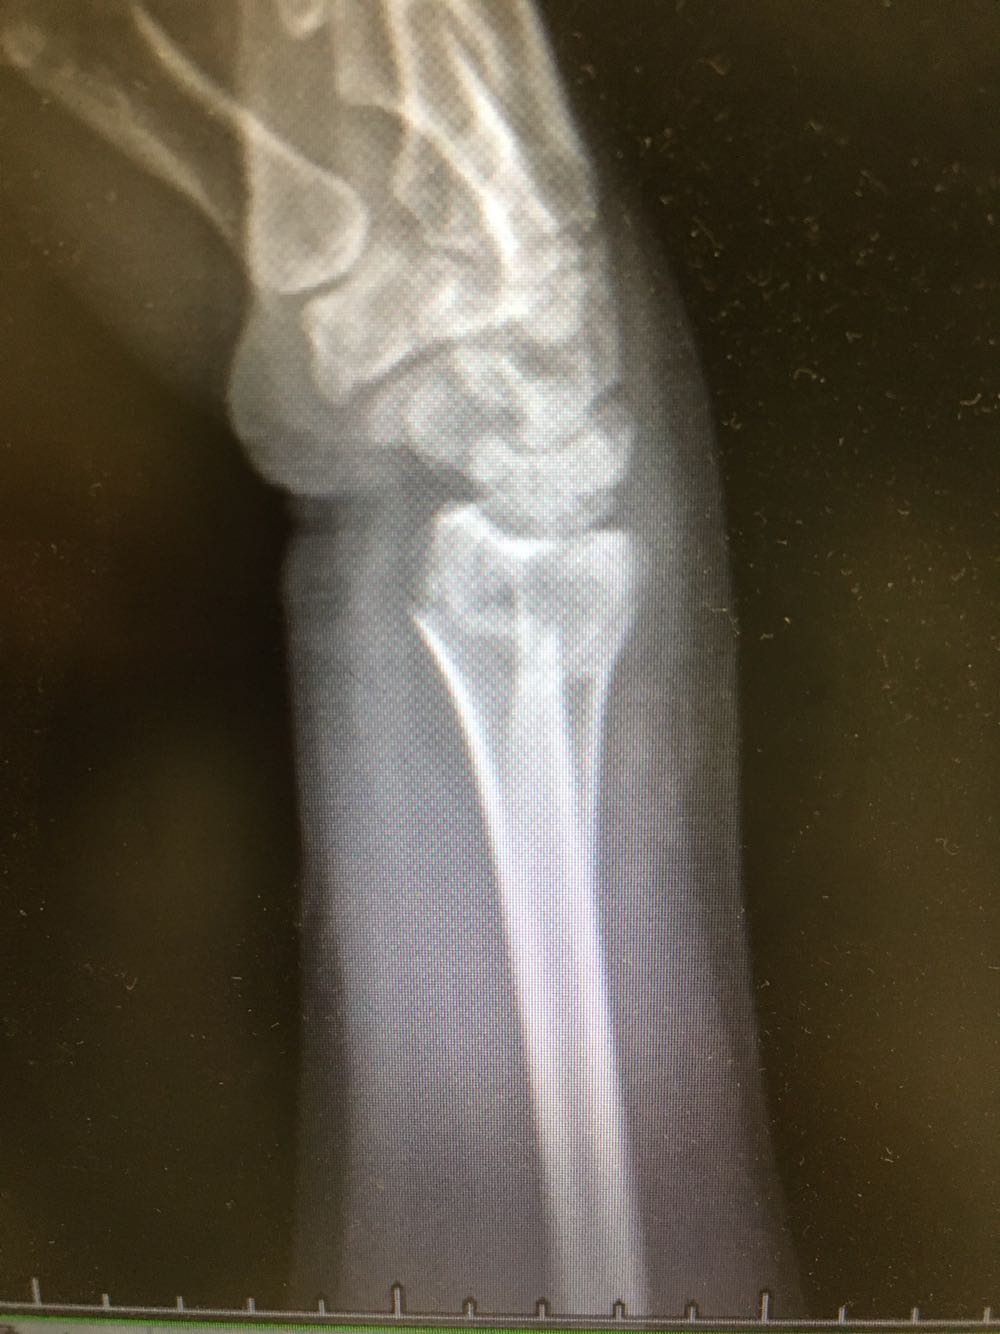

患者,女性,62岁 主诉:外伤致右腕部疼痛伴活动受限8小时 现病史:患者于8小时前受外伤后出现右侧腕部剧烈疼痛,后出现肿胀伴活动障碍,否认头晕头痛、恶心呕吐等不适,遂至我院就诊,查X片示:右侧尺桡骨远端骨折,现为进一步诊治收治入院,发病以来,神清,精神可,胃纳夜眠可,二便无殊,体重无明显变化。

查体:右侧腕部肿胀,压痛阳性,伴活动受限,远端肢体感觉及运动正常。 辅检:见现病史

诊断:右侧尺桡骨远端骨折 治疗:完善术前检查后行手术内固定